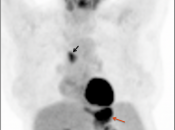

Recurrence & Restaging

• Restaging suspected recurrence.

• Distinguishing recurrence from post-therapeutic inflammation.